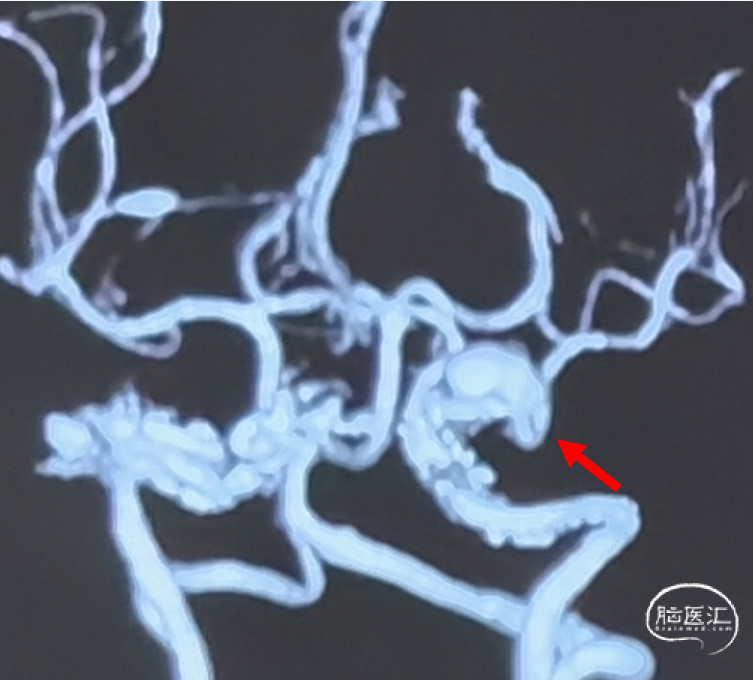

CTA

L ICA 3D

AN长径9.14mm

远端血管大脑中直径2.34mm、近端颈内末端4.25mm